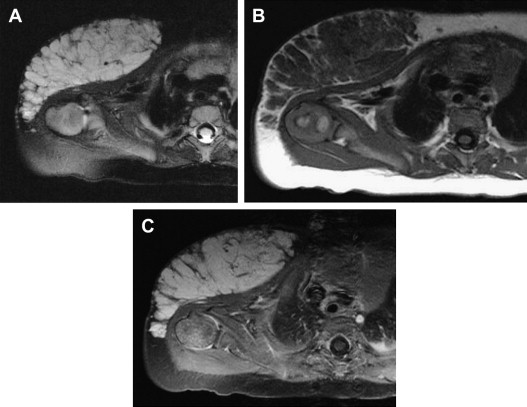

Proliferating infantile hemangiomas are lobulated hypervascular masses. On MRI studies, the lesions are isointense to muscle on T1-weighted sequences and hyperintense on T2-weighted sequences. High-flow central and peripheral vessels, seen as flow voids, are evident on T2-weighted sequences. After contrast administration, these masses enhance intensely and diffusely ( Fig. 2 ). In contrast to AVMs, arteriovenous shunting is not typically seen in infantile hemangioma.

During involution, infantile hemangiomas become more heterogeneous in appearance. MRI of involuting infantile hemangiomas demonstrates regions of fibrofatty deposition, manifested by areas of increased signal on T1-weighted sequences. Contrast enhancement diminishes and becomes inhomogeneous.